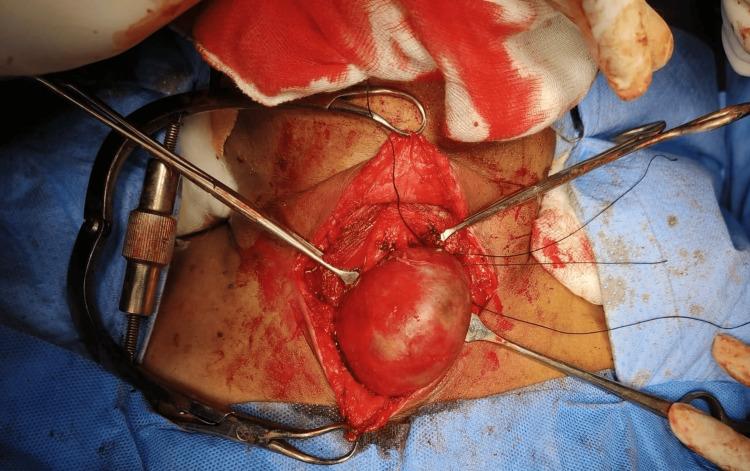

The incidence of mixed thyroid carcinoma of poorly differentiated thyroid carcinoma (PDTC) and papillary carcinoma thyroid is very unusual. PDTC exhibits a high degree of dedifferentiation and histopathological confirmation is done based on Turin's criteria. This type of carcinoma has a poor prognosis and the survival rates at five and ten years post-diagnosis are significantly lower compared to well-differentiated thyroid carcinomas. Surgery is the best mode of treatment at present. This is a case of a 71-year-old female who underwent total thyroidectomy with modified radical neck dissection which yielded a histopathological variant comprising PDTC and papillary thyroid carcinoma. The patient was followed up with a serial thyroglobulin antibody test and ultrasound of the neck at six months and one year, and both were found to be normal.

摘要

低分化甲状腺癌(PDTC)与甲状腺乳头状癌混合性甲状腺癌的发病率非常罕见。PDTC表现出高度的去分化,组织病理学诊断依据都灵标准进行。这种类型的癌预后较差,与高分化甲状腺癌相比,诊断后5年和10年的生存率显著降低。目前手术是最佳治疗方式。这是一例71岁女性患者,接受了全甲状腺切除术及改良根治性颈清扫术,术后病理结果为PDTC与甲状腺乳头状癌的组织病理学变异型。对该患者在术后6个月和1年进行了系列甲状腺球蛋白抗体检测及颈部超声检查进行随访,结果均正常。